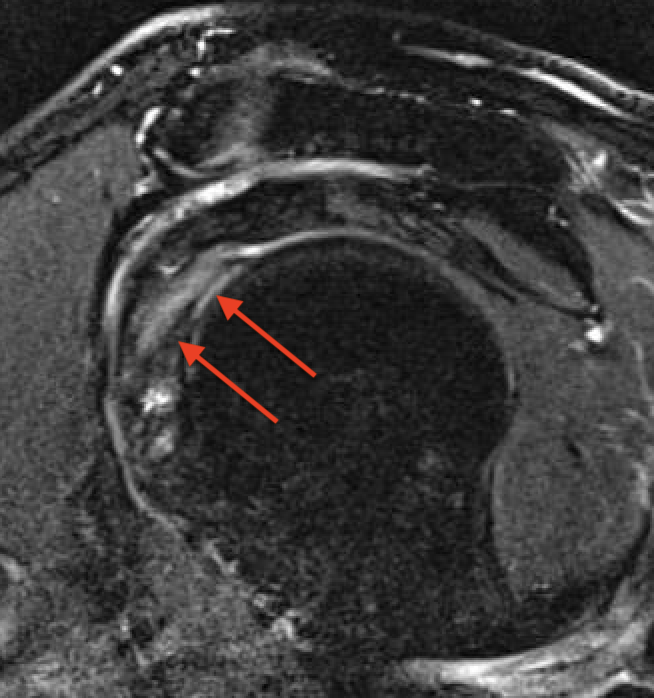

Tendonitis / tendinopathy

Normal

Tendonitis

Tendon thickening / tendinopathy

Sagittal MRI demonstrating severe LHB tendinopathy